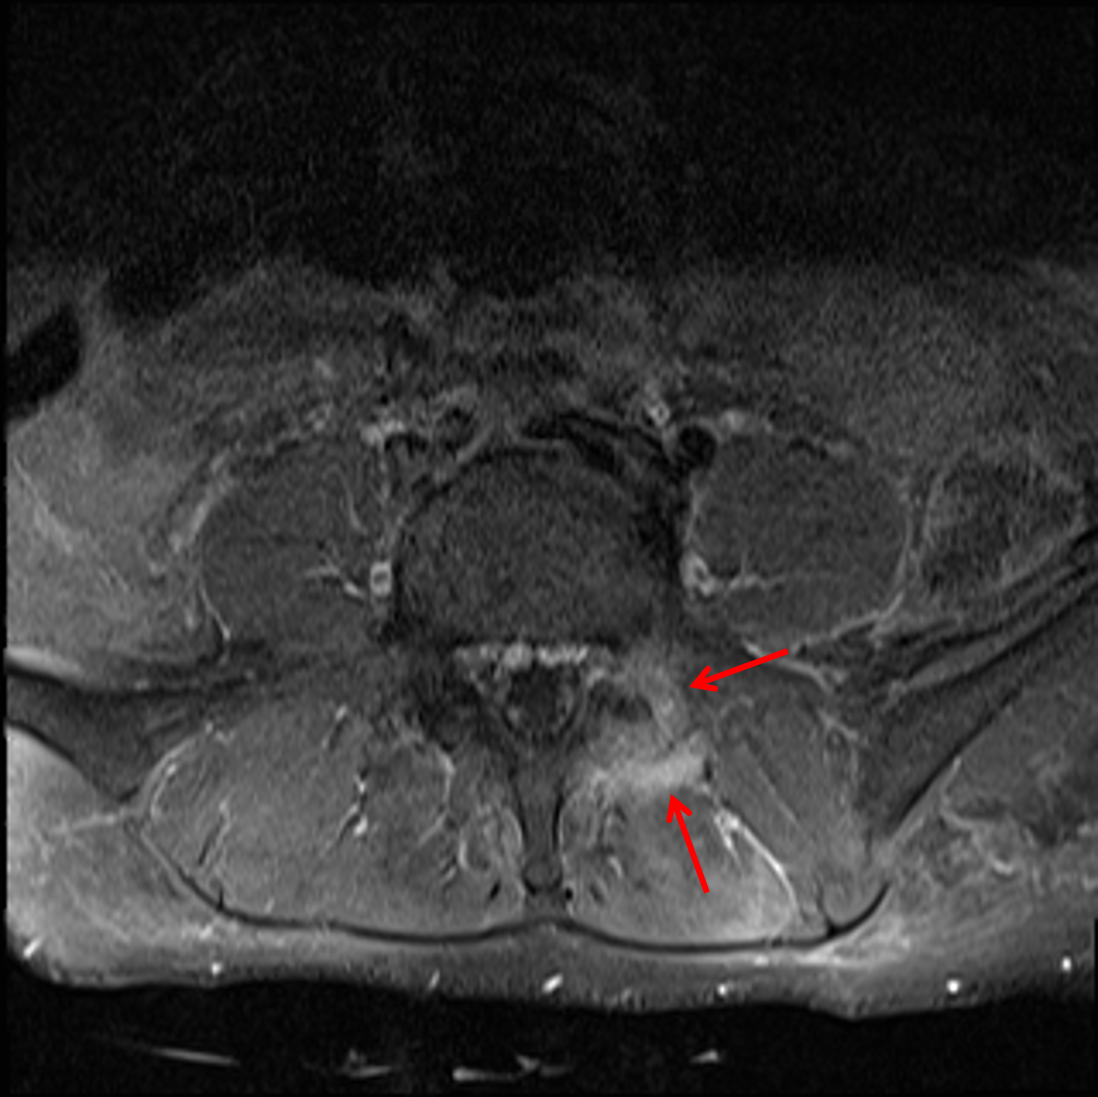

Casestacks.com. Wrist arthritis lateral xray eorif arthritic m19 evaluation clinical. Facet mri arthritis septic joint casestacks spine l5 s1 enhancement